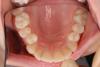

Ст@ся Опубликовано 21 сентября, 2012 Автор Поделиться Опубликовано 21 сентября, 2012 Кстати, полный вид на нижней челюсти:http://images.vfl.ru/ii/1348217827/7000df3b/948806_m.jpg Ссылка на комментарий